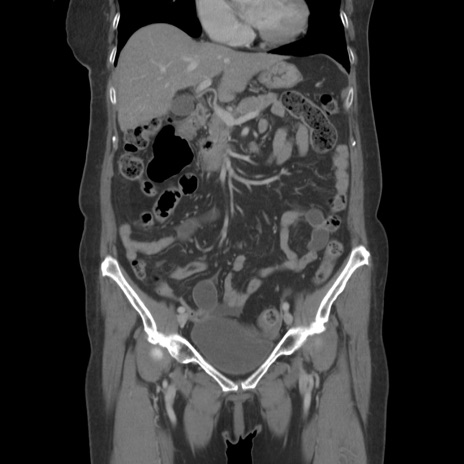

症例19(冠状断像)

【症例】80歳代女性

【主訴】下腹部痛

【現病歴】約8時間前より下腹部痛の出現あり、救急外来受診。

【既往歴】両側付属器切除

【身体所見】意識清明、下腹部正中に手術痕あり、その部位に一致して圧痛と反跳痛あり。腸蠕動音は亢進。

【データ】WBC 9300、CRP 0.15